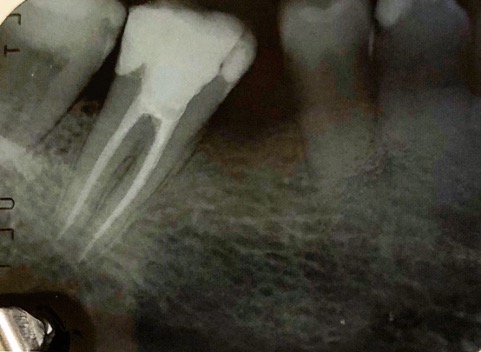

Un trattamento endodontico consiste nel salvare un dente compromesso da carie, traumi o fratture rimuovendone polpa e nervi infetti/infiammati responsabili di dolore, ascessi, cisti e granulomi.

Una corretta terapia canalare con un perfetto sigillo a livello degli apici delle radici è fondamentale. I denti devitalizzati impropriamente possono creare ulteriori problemi che poi andranno a ripercuotersi sulle cure effettuate successivamente come le ricostruzioni e le corone protesiche con conseguente fallimento del piano terapeutico.

Capita spesso di incontrare denti già devitalizzati in maniera impropria che necessitano, seppur asintomatici, di essere ritrattati per evitare che i granulomi infetti visibili radiograficamente si evolvano riassorbendo tutto l’osso sottostante.